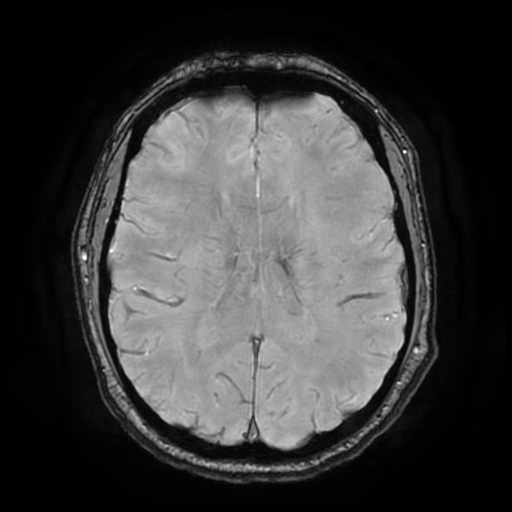

3. 🩸 Microbleeds em SWI (12-14 focos)

Centrum Semiovale bilateral 4-5 focos

Juxtacortical superior 3-4 focos

🩸 Microbleeds SWI

lesionBrain: 7 lesões focais

↔️

SWI Manual: 12-14 microbleeds

✅ Concordância parcial. lesionBrain detecta lesões maiores, mas subestima microbleeds pequenos (<2mm).

• Gliose pontina (SWI #32) - Achado patognomónico

• Microbleeds múltiplos (12-14 focos) em localizações típicas de LAD